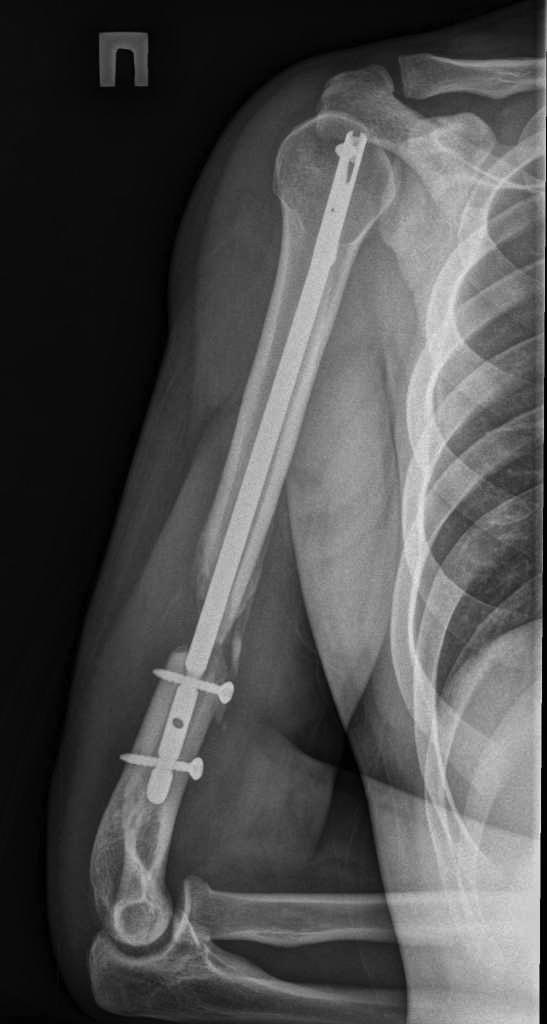

Перелом штифта

Пациент 25 лет, в сентябре 2012 г ДТП. Кроме всего прочего, открытый перелом правого плеча с дефектом костной ткани. При поступлении выполнено ПХО и ЧКО из 2 колец. После заживления раны выполнен БИОС плеча. Штифт сОлидный, Остеомед. Пару дней назад во время попытки открытия крышки банки (нагрузка по ротации) почувствовал боль в плече. Результат на снимке. Планируем удалить оба отломка (дистальный открыто) и перештифтовать более массивным штифтом. Вопрос №1: есть ли вариант в данном случае закрыто удалить дистальный франгмент НЕканюлированного штифта. Особых инструментов для удаления сломаных штифтов не имеем. Вопрос №2: как вариант рассматриваем выполнить ЧКО удалив предварительно только проксимальный фрагмент штифта. СтОит ли? Вариант накостного остеосинтеза с пластикой и без не рассматриваем. Спасибо за внимание.